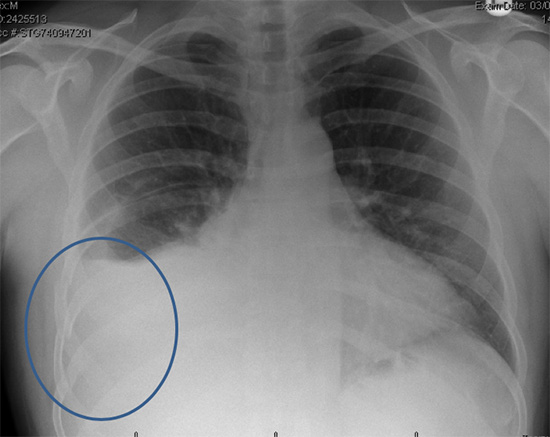

How to diagnose broken ribs. The doctor will first give you an exam to look. If you have a broken rib, symptoms such as bruising, pain and swelling are considered very Press on the injured area.

A broken rib typically causes sharp pain. To diagnose a rib injury, it’s best to see a medical professional who can look at your injuries with professional tools and technology. You may also feel or hear a crack or pop when the.

Take slow, deep breaths and cough regularly to expand your lungs, use an incentive spirometer if asked to do so, get up and move around when you’re not sleeping,. When visiting your doctor, they will most likely be able to diagnose your injury simply by pushing on your chest and doing a physical exam. The pain you feel with a broken rib typically occurs or even worsens when you: